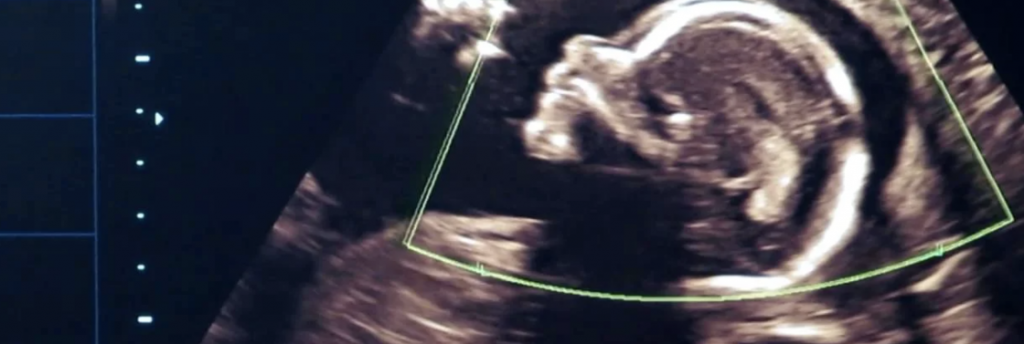

Ультразвуковое исследование – самый информативный и безопасный метод.

Исследование можно проводить, начиная с 16 дня после вязки. Но более точные данные получают на 25 день с момента оплодотворения – уже фиксируется сердцебиение, что говорит о жизнеспособности плода.

УЗИ позволяет выяснить:

Факт зачатия, что особенно важно бывает для кошек, которые забеременели в первый раз.

Многоплодная или малоплодная беременность.

Развитие органов плода, частоту сердцебиения.

Жизнеспособность котят и есть ли распад плода в матке.

Врожденные уродства.

Предполагаемую дату родов с точностью до 4 дней, даже если дата вязки неизвестна.

Оптимальную дату для кесарева сечения. С 55 дня вязки врач планирует дату для кесарева (при необходимости).